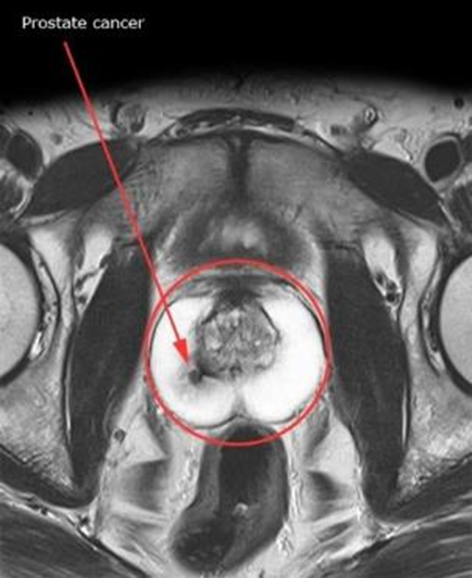

Prostate MRI

Multiparametric MRI is an accurate way of detecting and staging of prostate cancer. It is an extremely useful tool to direct the urologist to the exact area of concern, so an accurate representative biopsy result can be obtained. It can also indicate the degree of spread outside the prostate or if it is confined to the prostate, which can affect the management and treatment. Some prostate cancers are slow-growing and never spread beyond the prostate gland. Not all prostate cancers need treatment. Cancer is easier to treat and is more likely to be cured if it's diagnosed in the early stages of the disease.